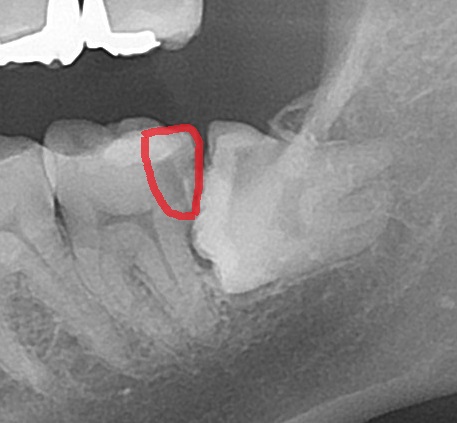

上記写真の親知らずの場合、親知らず自体が黒くなっているのが分かりますが、さらにレントゲン写真(エックス線)検査で歯の中の状態を見てみると

エックス線検査は見えない歯の内部が見えます。横向きに生えて、手前の歯にぶつかっているのが分かります。

こちらをよく見てみると、

赤い枠の部分が黒く抜けて見えますが、こちらは虫歯になっている場所です。虫歯で歯が溶けると、エックス線写真で黒く抜けた像になります。

親知らずが原因で手前の歯が虫歯になってしまっています。本人では気づけない虫歯となります。